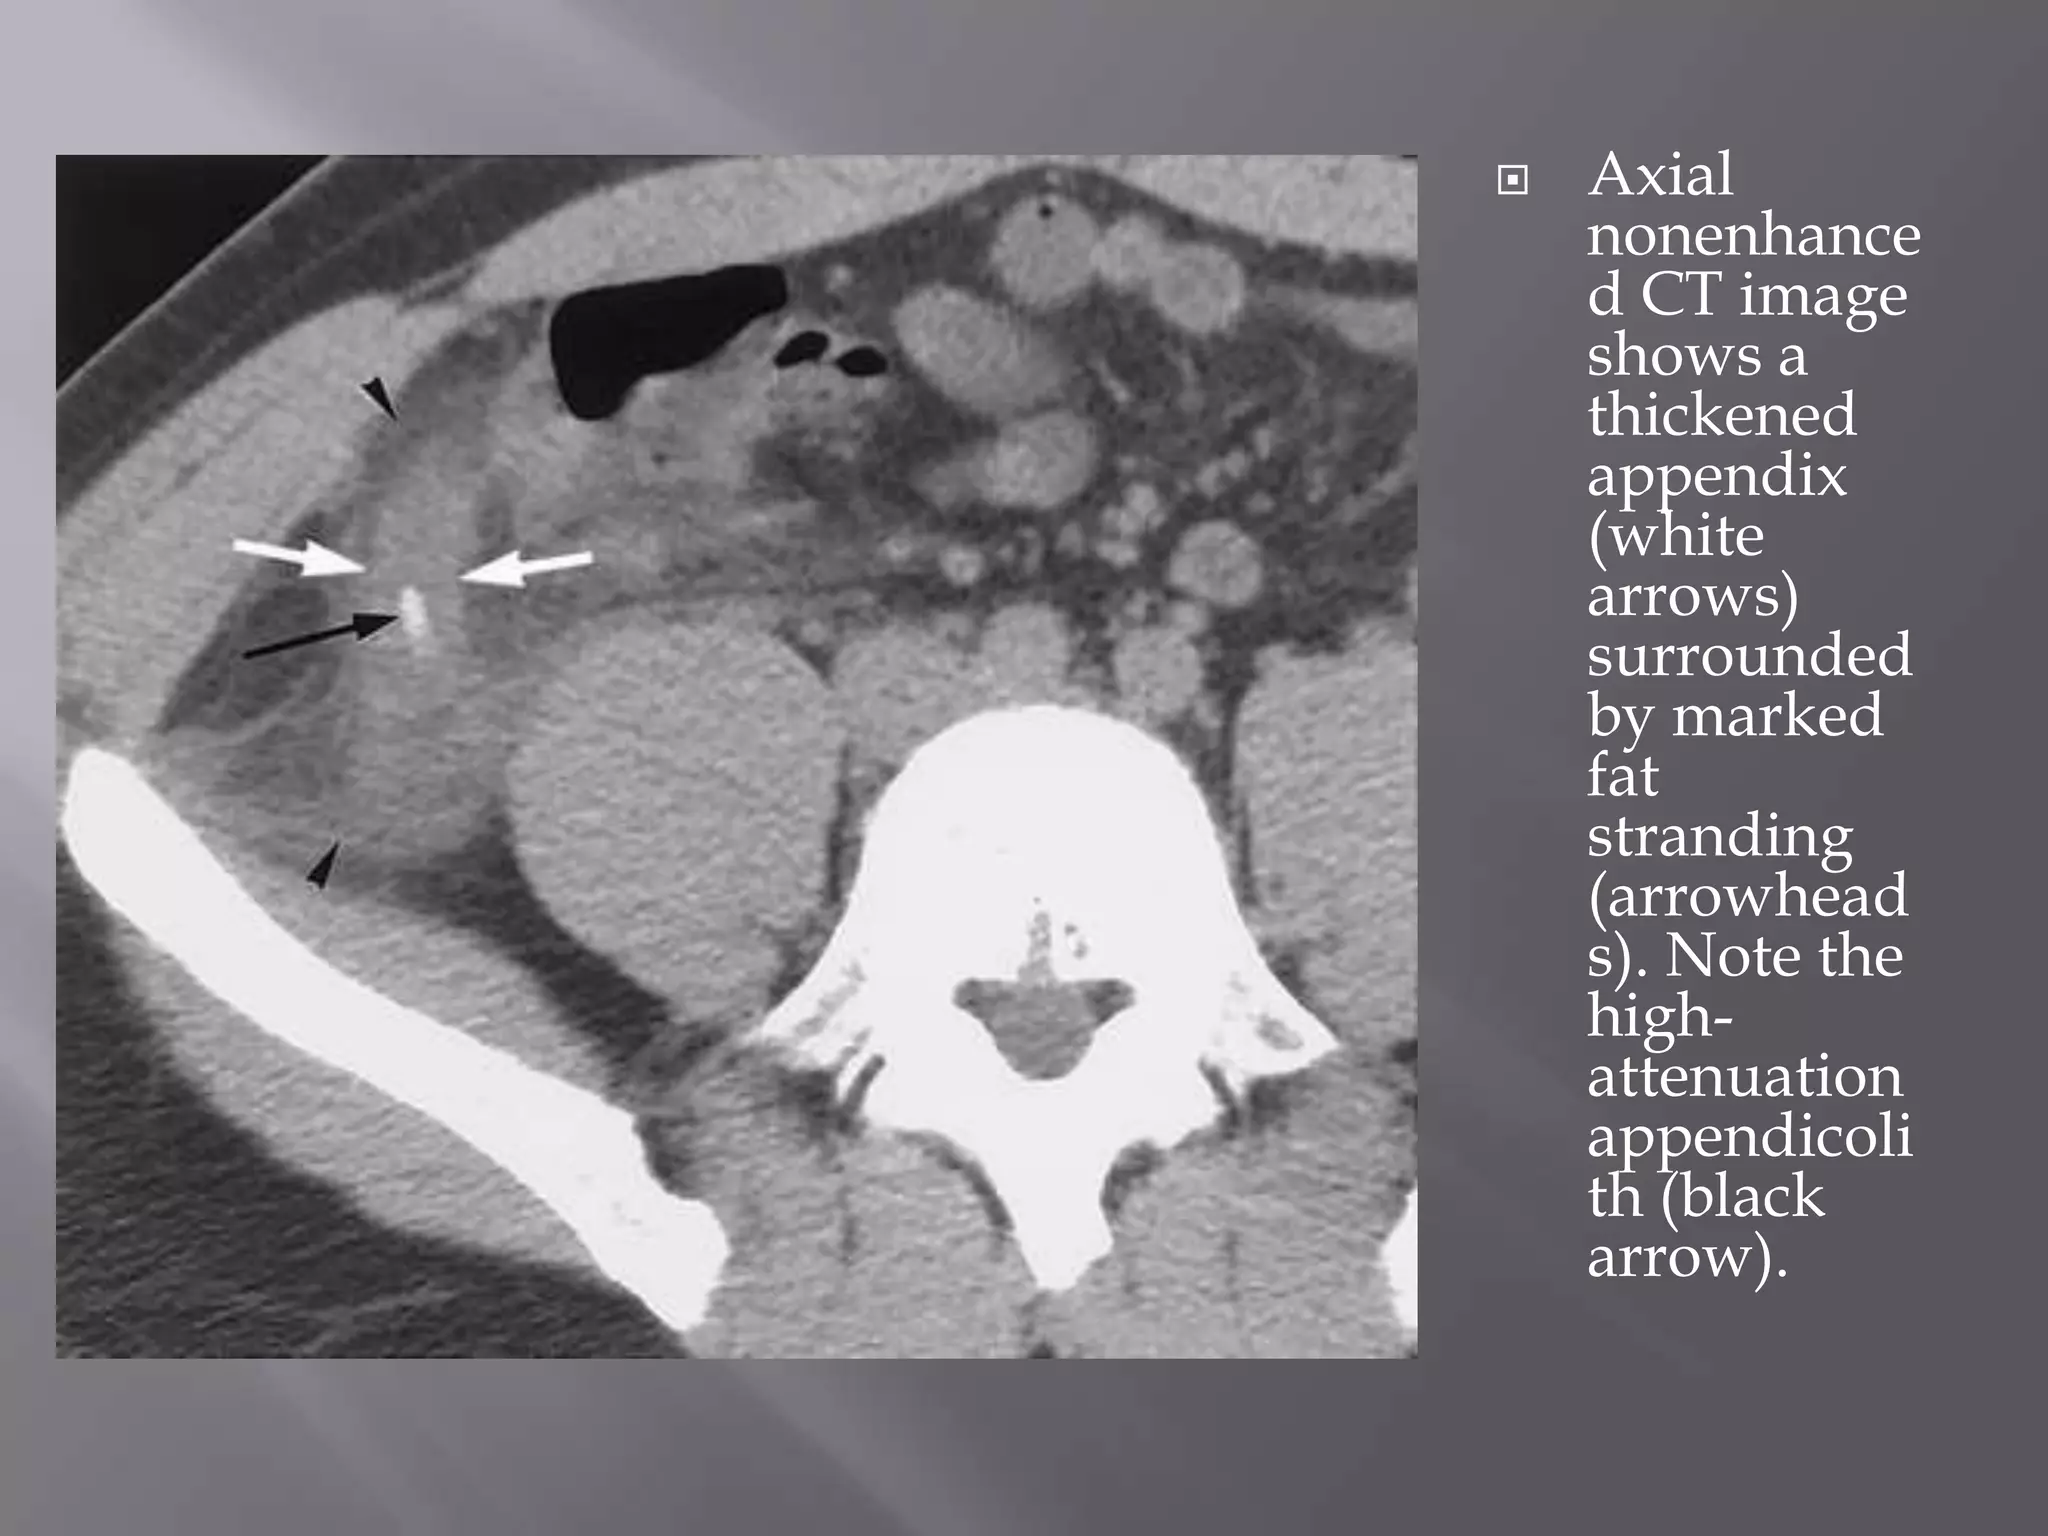

 CT Findings - Direct visualization of a dilated

 Other direct signs include an abnormally

 Secondary signs include appendicolith(s) or

 Axial

nonenhance

d CT image

shows a

thickened

appendix

(white

arrows)

surrounded

by marked

fat

stranding

(arrowhead

s). Note the

high-

attenuation

appendicoli

th (black

arrow).

 CT Findings- Direct visualization of a dilated (>6 mm in maximum diameter), fluid-filled appendix is the most specific.  Other direct signs include an abnormally thickened appendix, increased attenuation of the appendix after contrast material administration, and periappendicular fat stranding.  Secondary signs include appendicolith(s) or thickening of the cecal apex (cecal bar sign).

 Axial nonenhance d CTimage shows a thickened appendix (white arrows) surrounded by marked fat stranding (arrowhead s). Note the high- attenuation appendicoli th (black arrow).